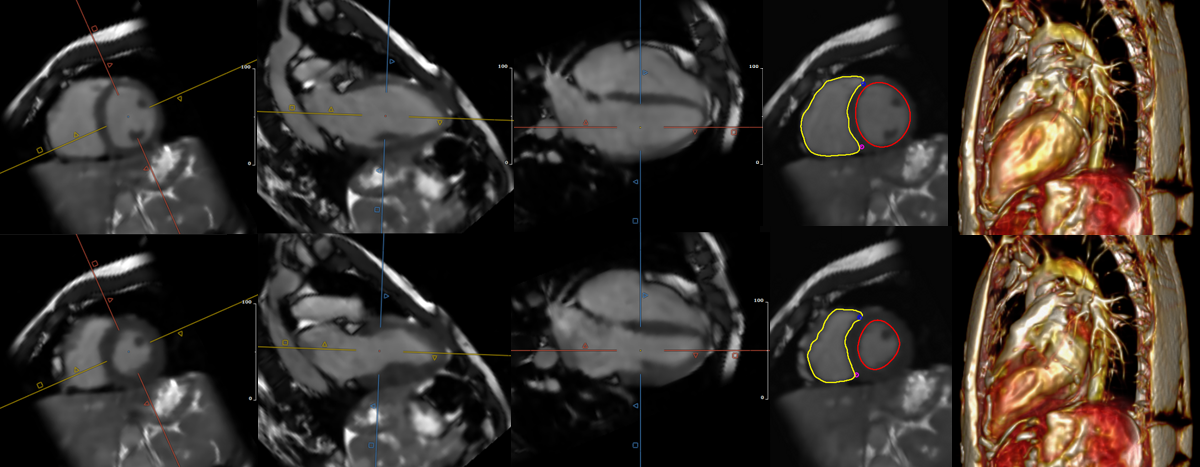

Results: 6 patients (1 Female, age 34±9y, BMI 27±6) were scanned at 1.5T (MAGNETOM Sola, Siemens Healthineers, Forchheim, Germany) with clinical indications of congenital heart disease and Myocarditis. Average breathhold durations were 18.7s and 17.3s for 1- and 2-BH scans respectively. Function parameters LVEF, LVEDV, RVEF and RVEDV as shown in Table 1 were calculated from 3D cine datasets after reformatting to short-axis slices with thickness matched to the clinical reference using Circle (Circle CVI Inc. Calgary, CA). Good agreement with standard clinical assessment was seen for both 1- and 2-BH scans, with slightly lower LV- and RVEF for the 3D approach (not statistically significant). Figure 3 shows an additional 3-BH scan in a patient with limited breathhold capabilities, underscoring the efficacy of inter-breathhold motion compensation.

Example for Diastolic (top row) and Systolic frames (bottom row) from a 2-BH whole heart 3D cine scan. Images were reformatted from the full 3D+time dataset, from left to right: Short axis, 2-chamber, 4-chamber, segmented short axis and sagittal MIP.

Results: 6 patients (1 Female, age 34±9y, BMI 27±6) were scanned at 1.5T (MAGNETOM Sola, Siemens Healthineers, Forchheim, Germany) with clinical indications of congenital heart disease and Myocarditis. Average breathhold durations were 18.7s and 17.3s for 1- and 2-BH scans respectively. Function parameters LVEF, LVEDV, RVEF and RVEDV as shown in Table 1 were calculated from 3D cine datasets after reformatting to short-axis slices with thickness matched to the clinical reference using Circle (Circle CVI Inc. Calgary, CA). Good agreement with standard clinical assessment was seen for both 1- and 2-BH scans, with slightly lower LV- and RVEF for the 3D approach (not statistically significant). Figure 3 shows an additional 3-BH scan in a patient with limited breathhold capabilities, underscoring the efficacy of inter-breathhold motion compensation.